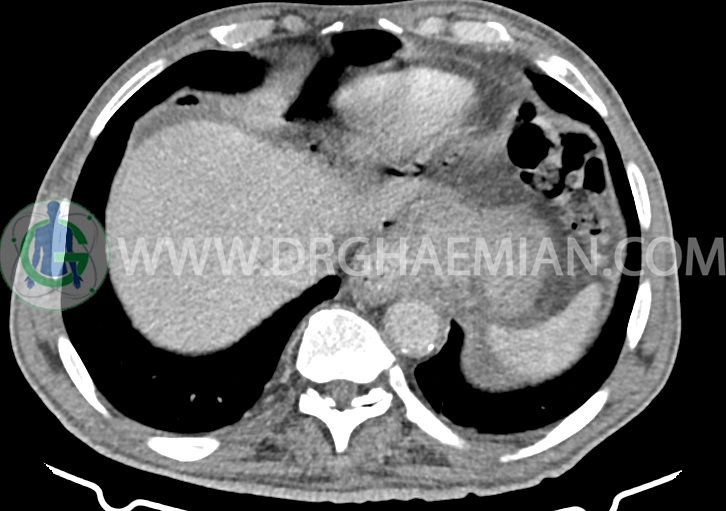

سی تی اسکن شکم و لگن با استفاده از اشعات ایکس تصاویر عرضی از ناحیه شکمی ایجاد میکند. در این کیس سرطان معده، لنفادنوپاتی، آدنوم، دیورتیکول، کیست های کورتیکال و آسیت دیده می شود.

در سی تی اسکن اسپیرال شکم و لگن با و بدون کنتراست خوراکی و وریدی – پروتکل ادرنال (مولتی دیدکتور 16 با مقاطع ظریف و بازسازی های ساژیتال و کرونال):

ضایعه ای در کبد، کیسه صفرا، مجاری صفراوی، طحال، کلیه ها، پانکراس و آدرنال راست مشهود نیست.

لنفادنوپاتی رژیونال فراون با حداکثر SAD=10mm

توده ایزودنس ( HU=30 ) به قطر 13mm در ادرنال چپ با enhancement قابل توجه در فاز پورتوونوس

( HU=130 ) و washout در فاز تاخیری 12 دقیقه ( HU= 60 ) مطرح کننده آدنوم benign

افزایش ضخامت ناحیه کاردیا ، فوندوس ، تنه و انتروم معده تا ناحیه پیلور همراه با امفیزم در پورتاهپاتیس ، فضای موریسون و بین معده و لوب چپ کبد

تصیویر چند دیورتیکول در کولون نزولی و سیگموئید

کیست های کورتیکال ساده به قطر 40mm در کلیه راست و به قطر 40mm در کلیه چپ

پنوموپریتوئن قابل توجه در قسمت فوقانی شکم و لگن

اسیت قابل توجه در حفره شکم و لگن

stomach cancer TNM staging :T4a – N3a-Mx